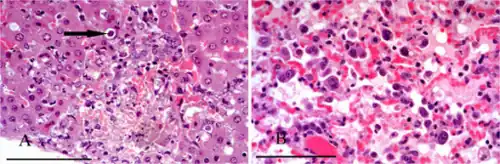

A parasitic disease, also known as parasitosis, is an infectious disease caused by parasites.

Medical parasitology is concerned with three major groups of parasites: parasitic protozoa, helminths, and parasitic arthropods.[2]

Parasitic diseases are thus considered those diseases that are caused by pathogens belonging taxonomically to either the animal kingdom, or the protozoan kingdom.[4]

Although organisms such as bacteria function as parasites, the usage of the term "parasitic disease" is usually more restricted. The three main types of organisms causing these conditions are protozoa (causing protozoan infection), helminths (helminthiasis), and ectoparasites.[8] Protozoa and helminths are usually endoparasites (usually living inside the body of the host), while ectoparasites usually live on the surface of the host. Protozoa are single-celled, microscopic organisms that belong to the kingdom Protista. Helminths on the other hand are macroscopic, multicellular organisms that belong to the kingdom Animalia. Protozoans obtain their required nutrients through pinocytosis and phagocytosis. Helminths of class Cestoidea and Trematoda absorb nutrients, whereas nematodes obtain needed nourishment through ingestion.[4] Occasionally the definition of "parasitic disease" is restricted to diseases due to endoparasites.[9]